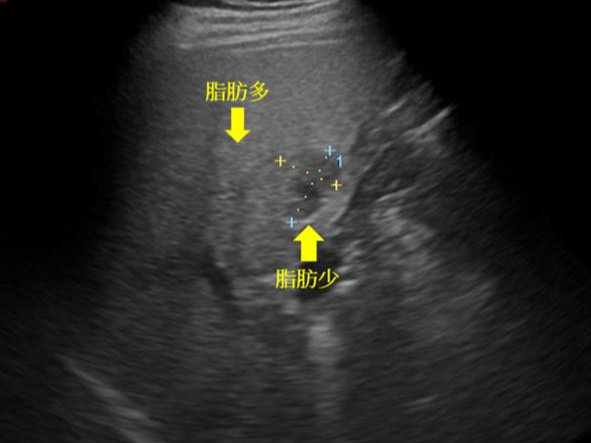

- 지방간

- 검사자 숙련도에 따라 영상 해석 편차

- 비만한 경우 영상 품질 저하